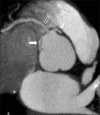

Left anterior descending (LAD) artery and left circumflex (LCx) coronary artery originating separately from the right sinus of valsalva is exceptionally rare and very few cases have been reported in the literature. Congenital coronary artery anomalies are generally incidental, uncommon, and asymptomatic. Some can cause severe potentially life-threatening symptoms such as myocardial ischemia and sudden cardiac death. The aberrant vessels that pass between the aorta and the pulmonary trunk pose a risk of sudden cardiac death, particularly if the vessel supplies the left coronary artery network. The electrocardiographically gated multi-detector computed tomography (MDCT) allows accurate and non-invasive depiction of coronary artery anomalies including origin, course, and termination. We report here a rare case of all three coronary arteries separately originating from the right coronary sinus, which was detected with MDCT.